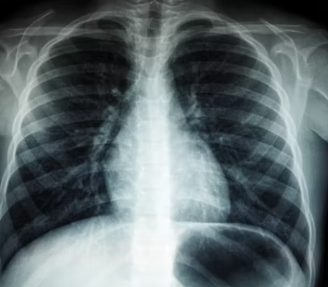

혈액 검사(염증 수치, 갑상선 호르몬), X-ray, MRI 등은 섬유근육통과 유사한 증상을 유발할 수 있는 다른 질환(류마티스 관절염, 갑상선 기능 저하증 등)을 배제하기 위해 시행될 수 있습니다.